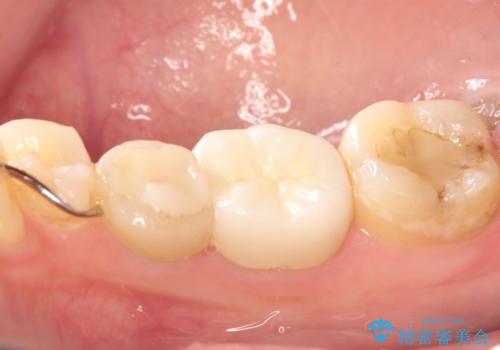

セラミッククラウンにて下顎の左右の歯にセラミッククラウンを装着する計画としました。

目立つところの銀歯がなくなり、審美的な改善ができました。